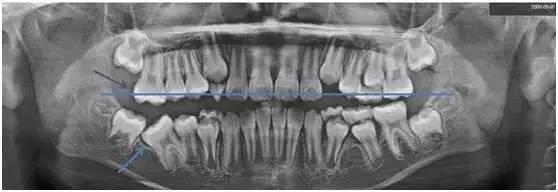

此时我才发现,她右侧下颌的“六龄齿”没有长出来,而其他三颗早已正常萌出了……这个情况引起了我的关注,我提议给她拍张X光片。

一看!果然右下“六龄齿”阻生(如图蓝色箭头处),我们向家长提出建议,必须进行早期治疗。

了解了“六龄齿”重要性之后,我们再回头看看小姑娘的X光片。

从X光片可以看到,小姑娘右下阻生的“六龄齿”,它的对合牙没有咬合接触,已经开始伸长。(以蓝色线为对标,紫色箭头指向的右上对合“六龄齿”较长)

再不处理,会占据右下阻生“六龄齿”的萌出空间,将来矫正难度将明显增大。